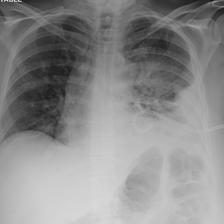

A.4 Data curation of imaging datasets

Large datasets often contain instances that are mislabelled or out of distribution [35]. We used BioViL-T to perform pairwise ranking of instances in MIMIC-CXR (Section 3.3, ) and selected representative examples found in the dataset. Our method is able to select the most appropriate image for a range of different image-acquisition or image-processing issues (Figure A.7).

We found that many lateral acquisitions in the dataset were unexpectedly labelled as frontal (Figure 7(a)). Some images contained only noise (Figure 7(b)), non-human samples (Figures 7(d) and 7(e)) or incorrect anatomy (Figure 7(g)). Often, acquisitions with an incomplete field of view (FOV) (i.e., the lungs are not completely visible) were repeated (Figure 7(c)). Lastly, post-processed images were detected by the algorithm such as contrast-enhanced scans (Figure 7(i)) that are not often used for diagnostic purposes in clinical practice.